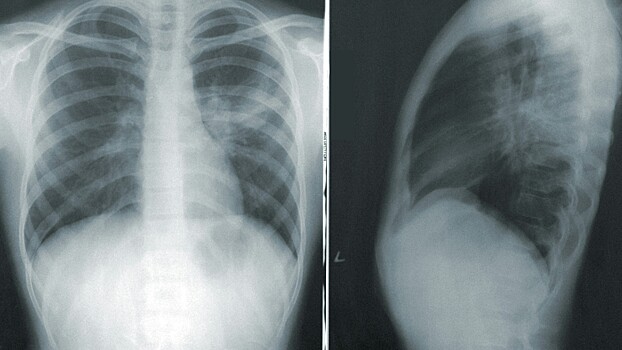

Но ведь опухоль на первой и второй стадии может достигать размеров от 3 до 6 см. Это достаточно большие опухоли, неужели их не видно на рентгене или флюорографии на этих стадиях?

— Их видно. Проблема заключается в том, что размер опухоли — это только часть проблемы. Вторая и третья части — это распространение опухоли и ее гистологическая структура, наличие метастазов. Размер опухоли напрямую коррелирует с распространенностью. То есть чем больше размер опухоли, тем чаще мы встречаемся с наличием отдаленных метастазов.

Поэтому общее правило для всех онкологических заболеваний — не дожидаться, когда опухоль достигнет больших размеров, а выявлять эту опухоль на предельно ранних стадиях. И вот с этим в рентгенографии очень большая проблема: найти маленький, сантиметровый или даже иногда двухсантиметровый одиночный очаг в легочной ткани очень сложно. И даже самые современные аппараты часто не позволяют точно и своевременно это сделать. Это не значит, что найти маленький очаг на рентгенограмме невозможно, но это скорее исключение, чем правило.

Это подтверждают исследования ученых РМАНПО, НМИЦ онкологии им. Блохина, Российского биотехнологического университета и компании «АльфаСтрахование-ОМС». Согласно данным исследования, рентгенография и флюорография органов грудной клетки совсем не «видят» рак легкого на первой стадии, пропускают большинство случаев рака легкого на второй стадии и половину случаев на третьей. С помощью обычной рентгенографии не удалось достоверно определить признаки рака легкого на ранних стадиях в 84,3% случаев. Вероятно, из-за неэффективности такой диагностики одногодичная летальность с момента установления диагноза «рак легкого» в два раза превышает данный показатель у онкологических пациентов.

— Нет, рак легкого можно и необходимо выявлять при рентгенографии. Сегодня именно так и происходит в обычной практике. Но мы говорим о суперранней диагностике, когда размеры очага в легком не превышают 1–2 см. Именно такие одиночные очаги труднее всего заметить на рентгеновском снимке. Для более крупных образований рентгенография — вполне надежный метод диагностики. Нельзя забывать, что во второй половине прошлого века она сыграла колоссальную роль в ранней (по тем представлениям) диагностике заболеваний органов дыхания, будь то рак легкого или туберкулез. Вся система раннего выявления этих заболевания в позднем СССР была основана именно на проверочной флюорографии.

При этом сегодня есть способ, который может существенно улучшить диагностику рака легкого на гораздо более ранней стадии — это низкодозная компьютерная томография (НДКТ). Ее внедрение в профилактические мероприятия позволит увеличить выявляемость рака легкого на ранних стадиях в два-три раза.